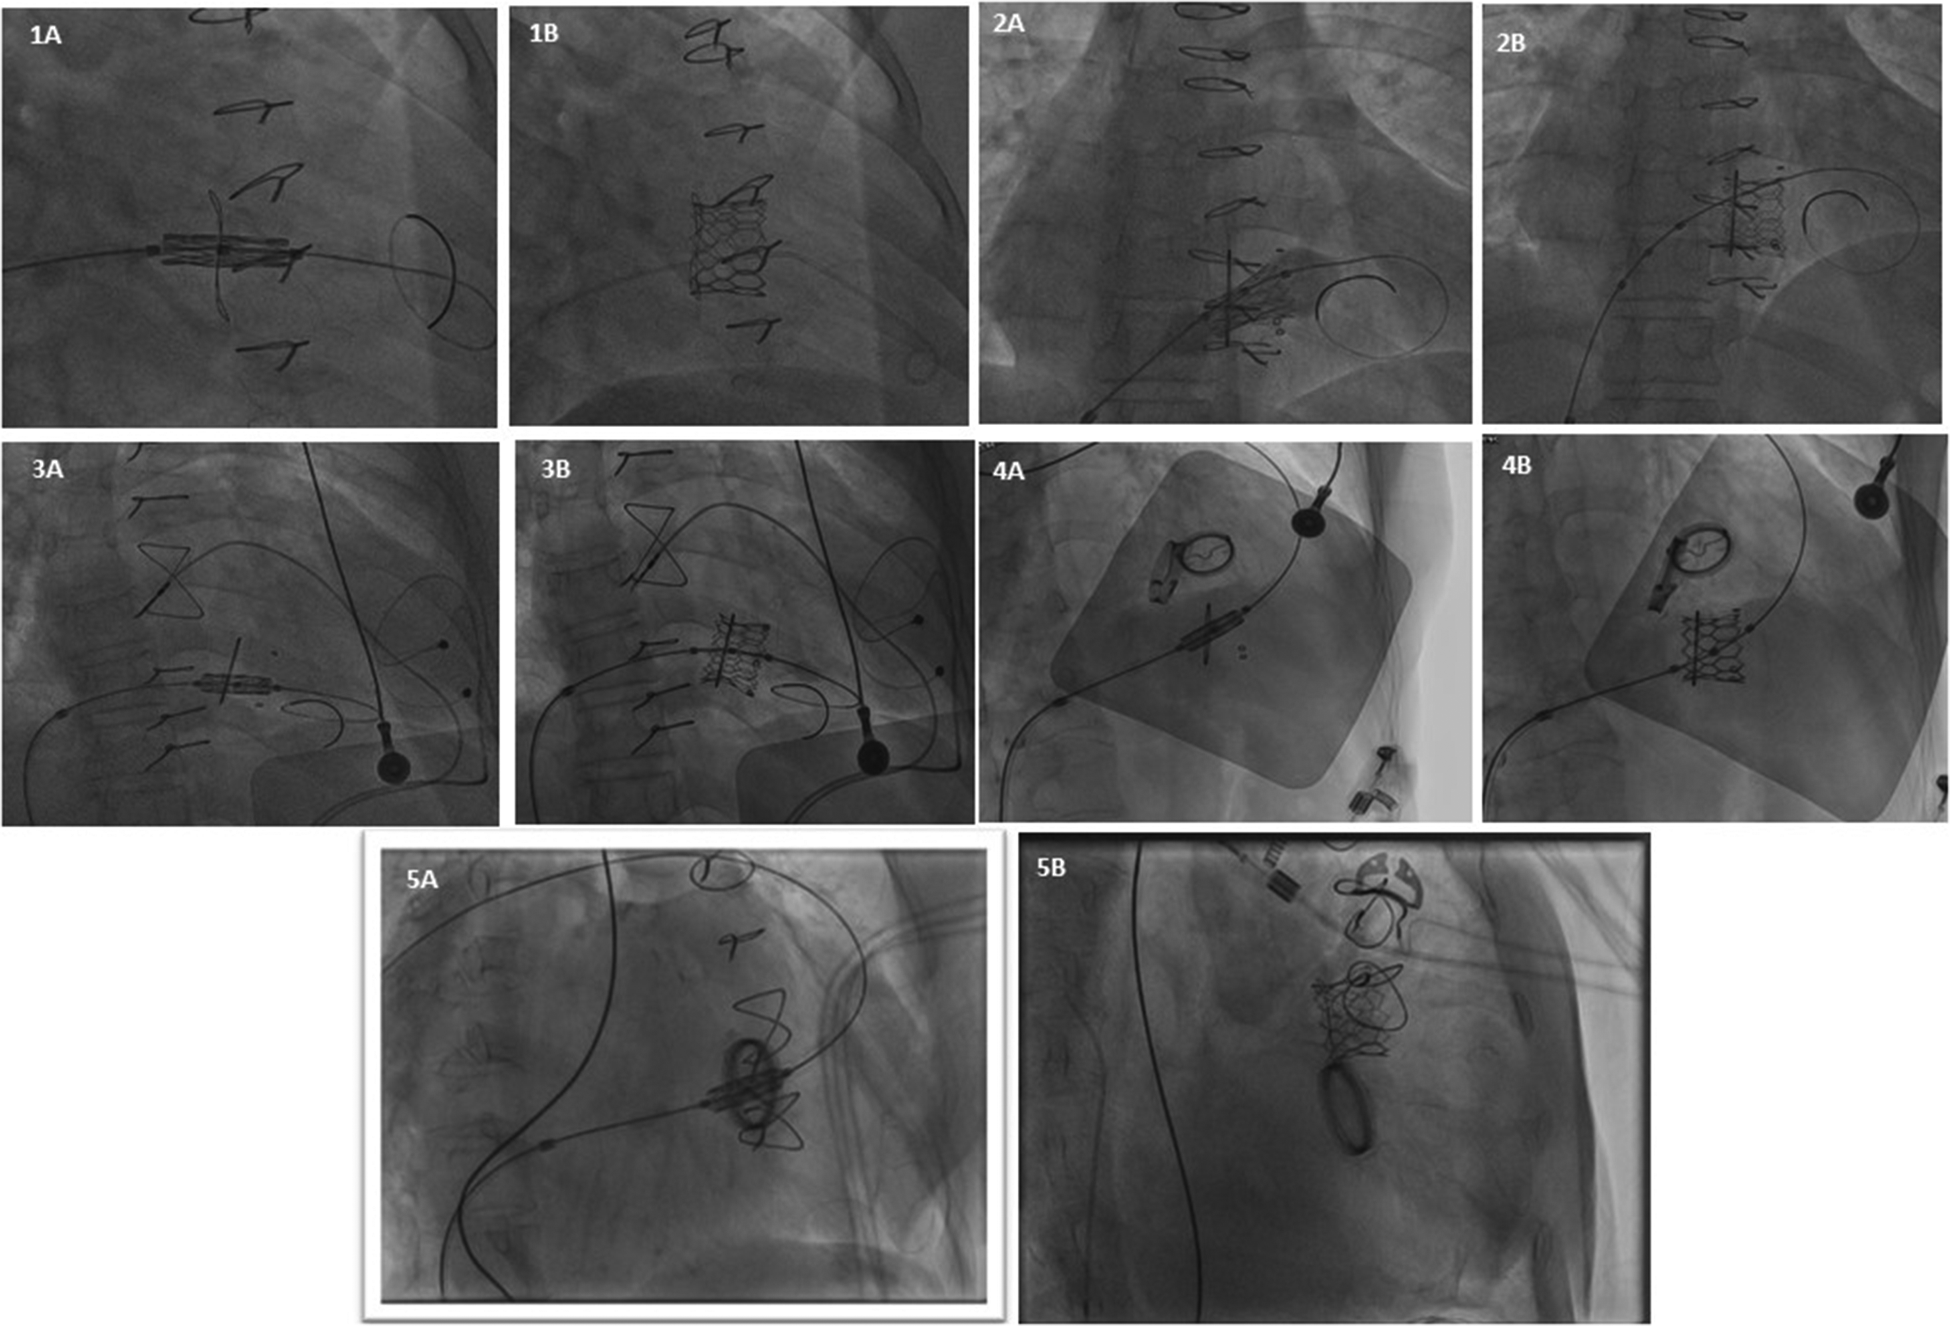

Figure 2

Represents fluoroscopic imaging after VIV implantation of all 5 patients (case 1 to case 5).

A 40-year-old female presented to our center with atrial fibrillation, symptomatic congestive heart failure, New York Heart Association (NYHA) functional class IV and tricuspid regurgitation due to a failed 33 mm Pericarbon More™ (Sorin Group, Italy) BHV [Figure 1(i)] surgically replaced 9 years ago (Ebstein’s anomaly) as a surgical indication. A 29 mm BE Myval THV (−0.5% downsizing) with 2 ml mixed contrast + saline was chosen and successfully implanted under local anesthesia under fluoroscopic guidance (Table 1, Figures 2: 1A,B). No pacing was required for the inflation of BE THV. No significant paravalvular leak (PVL) nor conduction disturbances were reported. The patient was discharged 7 days after the procedure on oral anticoagulant therapy: Vitamin K antagonists (VKA). Clinical and echocardiographic results at 6 months and 1-year are reported in Table 2.

A 49-year-old female with prior tricuspid valve replacement (8 years back) with a surgical bioprosthesis Hancock II 31 mm [Figure 1(ii)] (associated with Glenn’s procedure because of Ebstein’s anomaly) was admitted to our hospital. Her presenting symptoms were exertional dyspnea (NYHA III) and atrial flutter. On her echocardiogram, a degenerated BHV with mixed tricuspid valve disease (stenosis and regurgitation) was revealed. Although the patient was young, the local heart team decided for transcatheter ViV implantation. A 29 mm Myval THV (−1.7% of downsizing) plus 3 ml mixed contrast + saline was successfully implanted (no trans-valvular gradient, PVL or conduction disturbances) within the degenerated BHV [Table 1, Figures 2: 2A,B]. Pacing was not performed for the deployment of BE THV. A day before transcatheter tricuspid ViV implantation, successful transcatheter radiofrequency ablation of the atrial flutter was performed (Table 1). The patient was discharged after 7 days with oral anticoagulant therapy (VKA). At 6 months and 1-year follow-up, symptoms significantly improved with no echocardiographic signs of ViV deterioration (Table 2).

Eight years later, the patient was admitted with complaints of exertional dyspnea (NYHA III) and bilateral limb oedema. Transthoracic echocardiography revealed a severe degeneration of the surgical BHV. The institute’s heart team decided to proceed with ViV procedure. For this patient, a 29 mm Myval THV (0.1% of oversizing) was chosen and effectively implanted, without pacing (Table 1, Figures 2: 3A,B). The patient was discharged on oral anticoagulant therapy (VKA) 3 days later with good outcomes for up to 1 year (Table 2).

A 48-year-old female with diseased aortic and mitral valves (rheumatic etiology) underwent replacement of the respective valves with mechanical heart valves 16 years ago. Some years later, the patient developed symptomatic, severe tricuspid regurgitation with signs of congestive heart failure. Re-do surgery was required and a Hancock II 27 mm BHV was implanted [Figure 1(ii)] at the tricuspid position. Five years later, the patient was admitted to our center because of atrial fibrillation and exertional dyspnea (NYHA III). A degenerated BHV with severe regurgitation was detected and the patient was recommended for a ViV procedure. According to the BHV size measurements, a 24.5 mm BE Myval THV (7.1% degree of oversizing) was chosen for this young patient. The transcatheter tricuspid ViV implantation was effectively performed under fluoroscopic guidance (Table 1, Figures 2: 4A,B) without pacing. No major complications occurred during hospitalization and the patient was discharged after 4 days on oral anticoagulant therapy (VKA). At 1-year follow-up NYHA class improved while no PVL or significant gradient was noted in the echocardiography report (Table 2).

A 70-year-old female with severe, symptomatic mitral stenosis (rheumatic etiology) underwent surgical commissurotomy. Almost 17 years later, the patient developed symptomatic mitral stenosis and tricuspid regurgitation requiring surgical replacement of both valves {mechanical prosthesis Carbomedics 27 mm in mitral position and Pericarbon More 29 mm in tricuspid position [Figure 1(ii)]. Some years later, a stenotic degeneration of the tricuspid BHV occurred. The patient was referred for ViV procedure and a 27.5 mm BE Myval THV (12.5% degree of oversizing) was chosen. After balloon pre-dilatation with a 25 × 40 mm Mammoth balloon (Meril Life Sciences Pvt. Ltd., India), the BE Myval THV was successfully implanted, without pacing (Table 1, Figures 2: 5A,B) but three hours after the procedure, due to moderate femoral vein bleeding, two units of packed red blood cells were transfused, and surgical intervention was needed to manage this complication. Seven days after the procedure, the patient was discharged on anticoagulant therapy (VKA) (Table 2). During the 1-year follow-up, it was reported that the patient had died (Table 2).